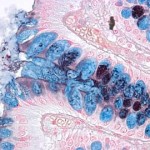

El intestino humano es el hogar de un ecosistema lleno de microbios que está íntimamente involucrados en la salud humana y la enfermedad. Pero mientras que la microbiota intestinal está interactuando con nuestro cuerpo, también están bajo constante ataque de los virus. En un estudio publicado en línea de Investigación inGenome, los investigadores han analizado un sistema inmune bacteriana, revelando un conjunto común de los virus asociados con la flora intestinal en la población global.

En este informe, un equipo de científicos de Israel ha tomado ventaja de la información codificada en un sistema inmune bacteriana a arrojar nueva luz sobre estas cuestiones. Las bacterias pueden «robar» pequeños fragmentos de ADN de los fagos que las atacan, y utilizar estas piezas robadas para reconocer y responder al atacante, de una manera similar al uso de anticuerpos por el sistema inmune humano. Las piezas robadas de ADN se almacenan en lugares específicos en el genoma de la bacteria llamada loci CRISPR (agrupados regularmente intercalados repeticiones palindrómicas cortas).